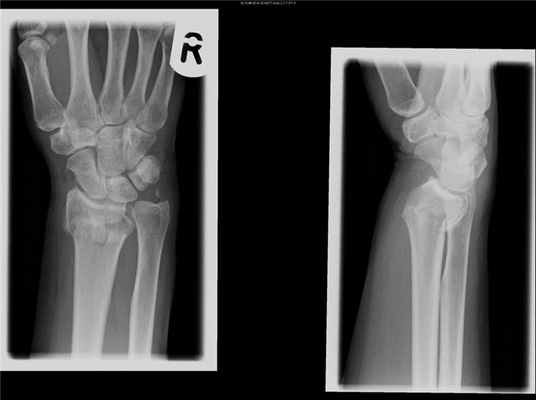

Перелом лучевой кости «в типичном месте» — перелом лучевой кости на 2–3 см проксимальнее суставной поверхности • Частота. 15–20% всех переломов. У пожилых женщин возникает в 2–3 раза чаще, чем у мужчин • Причины: падение на вытянутую руку с согнутой кистью • Патоморфология •• При падении на кисть в положении разгибания возникает разгибательный перелом Коллиса — дистальный отломок смещается в тыльную и лучевую сторону и супинирует, центральный смещается в ладонно-локтевую сторону •• При падении на кисть в положении ладонного сгибания возникает сгибательный перелом Смита — дистальный отломок смещается в ладонную сторону и пронирует, центральный — в тыльную сторону и супинирует • Клиническая картина: вилкообразная или штыкообразная деформация, при переломе Коллиса пальпируется на тыльной поверхности дистальный отломок, на ладонной — проксимальный, при переломе Смита дистальный отломок пальпируется на ладонной поверхности, проксимальный — на тыльной; резкая болезненность при пальпации лучевой кости и шиловидного отростка, осевой нагрузке. Часто повреждаются срединный нерв, межкостные ветви срединного и лучевого нервов (неврит Турнера) — резкие боли, парестезии, зоны анестезии, остеопороз костей кисти, ограничение движения IV пальца • Лечение •• Перелом без смещения — гипсовая лонгета (предплечье в среднем положении между супинацией и пронацией, кисть — лёгкое тыльное сгибание) на 3–4 нед •• Переломы со смещением — ручная или аппаратная репозиция, гипсовая повязка на 4–5 нед •• Неврит Турнера — витамины группы В, неостигмина метилсульфат, анаболические гормоны, тиреокальцитонин, прокаин внутрикостно.